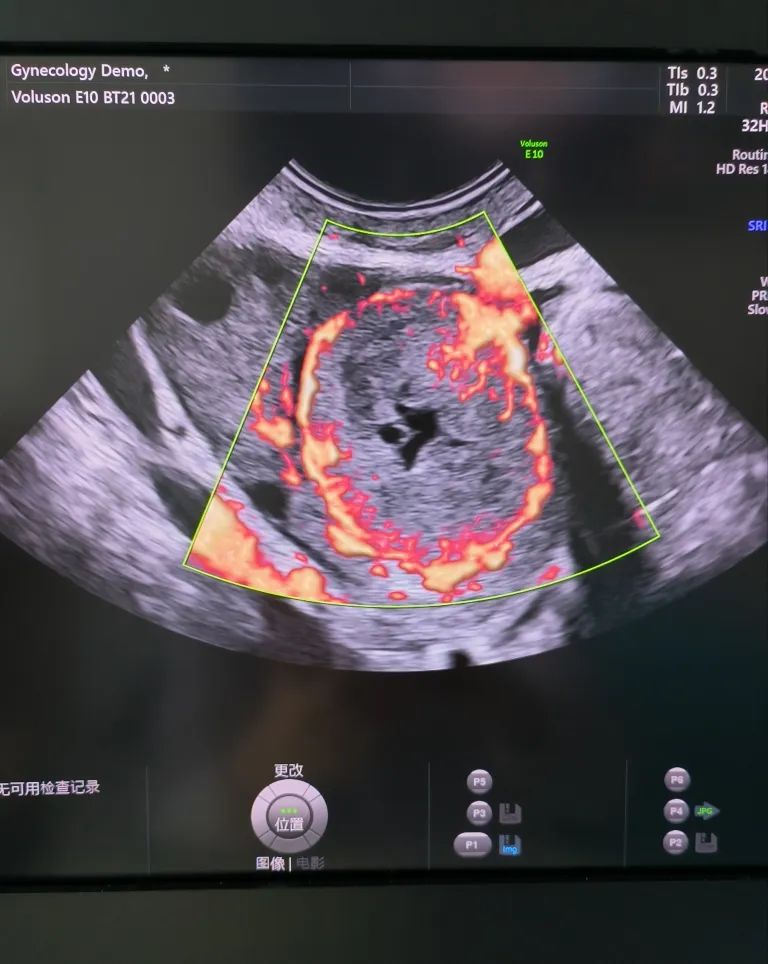

經(jīng)陰道超聲是在陰道超聲探頭上套上避孕套,將探頭伸入陰道進(jìn)行檢查。由于探頭位置接近子宮和卵巢,圖像更清晰,檢查結(jié)果更準(zhǔn)確。而且不需要憋尿,相對節(jié)省時間。所以現(xiàn)在大部分醫(yī)院對有性生活史的婦女更愿意開展經(jīng)陰道超聲檢查。